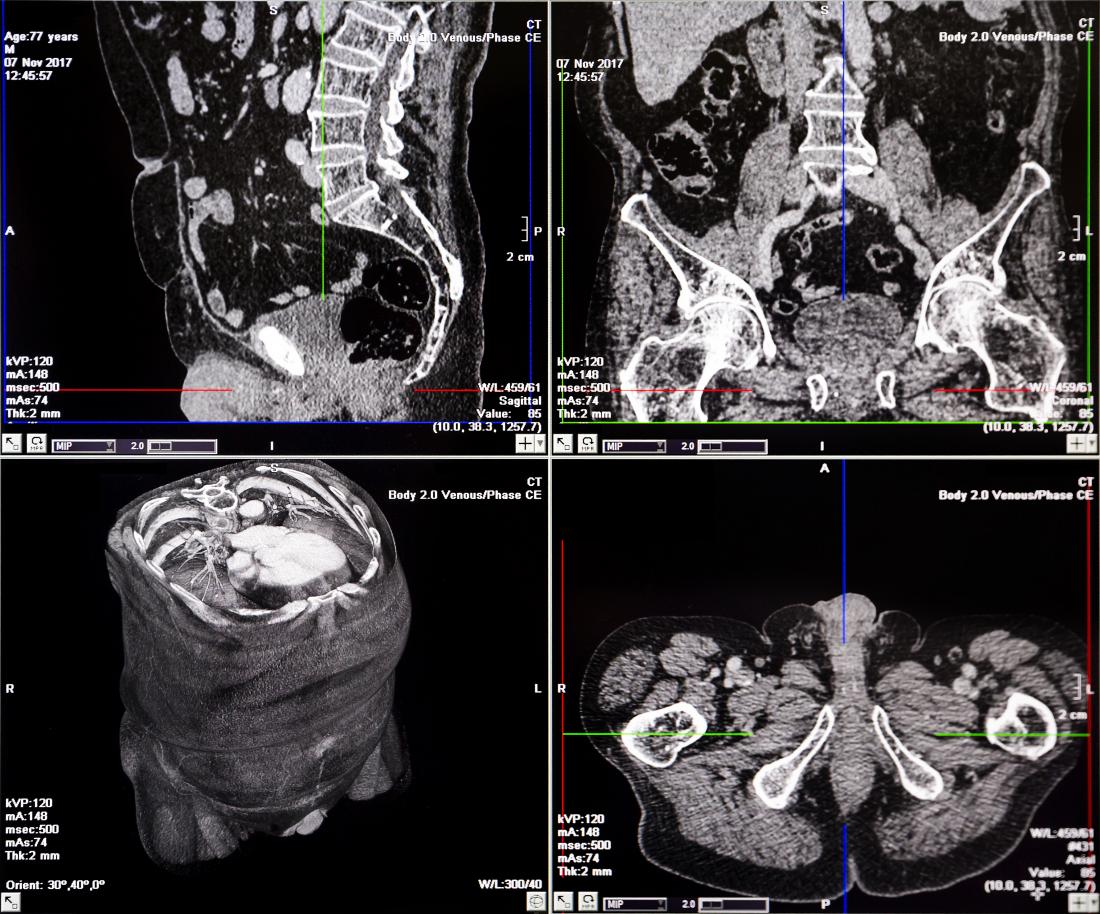

Computed Tomography scan combines the us of a digital computer together with a rotating X-ray device to create detailed cross sectional images or slices of the different organs.

CT scan is a painless and less sensitive to patient than MRI.Among the various imaging techniques CT has the unique ability to image a combination of soft tissues,bone,and blood vessels.Here no radiation remains in the patient body after a CT examination.X-ray image of the head can only show the dense bone structure of the skull.Magnetic resonance (MR) imaging does an excellent job of showing blood vessels and soft tissue,but MR does not give as much details of bony structures such as the skull.CT images of the head allow the physicians to see soft-tissues ,anatomic structures like the brain’s ventricles,of grey and white matter.And,CT can provide detailed cross sectional images and diagnostic information for nearly every part of the body.

⭐CT imaging and CT angiography and finding a greater role in the detection, diagnosis and treatment of heart disease, vascular diseases and acute stroke,which lead to stroke,gangrene or kidney failure.